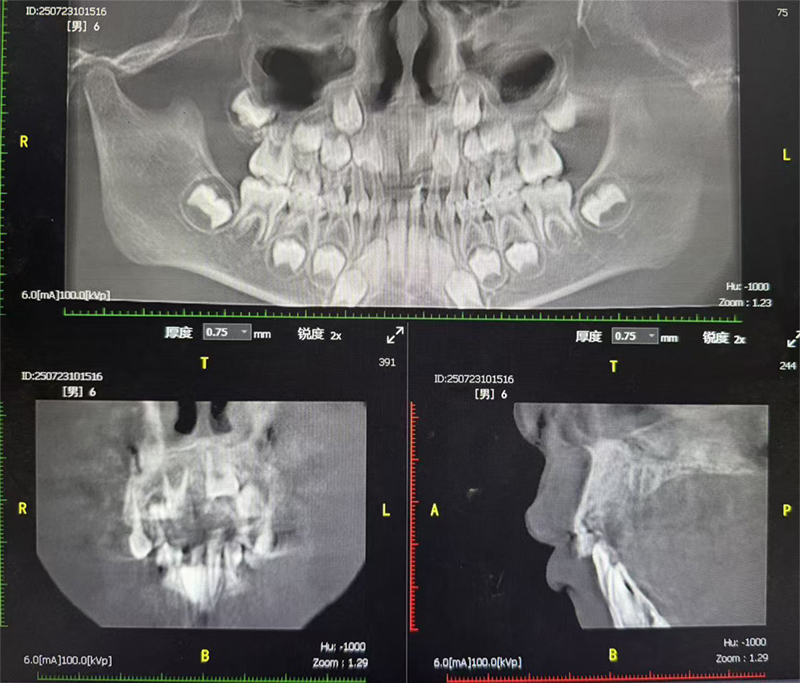

该名6岁男童因牙齿发育异常前往祁东县中医医院口腔科就诊,经口腔CT检查发现,其门牙区域存在2颗埋伏多生牙。在临床上,门牙区域生长的埋伏多生牙若不加以干预,影响恒牙的生长,甚至可能会形成颌骨囊肿的情况。此外,这颗埋伏多生牙与恒牙牙胚极易混淆,难以分辨,给手术增加了极大难度,对口腔科医生的技术水平提出了很高要求。

术前口腔CT检查

由于患儿年龄较小,配合度低,且多生牙位置特殊、与恒牙牙胚难以区分,手术难度极大。传统局麻下手术可能因患儿哭闹、躁动导致视野不清,增加手术风险和并发症发生率。为确保手术安全、精准进行,口腔科陈志华副主任医师联合麻醉科进行多学科会诊,麻醉前对患者进行了全面评估身体状况和全面体检,充分考量患儿身体状况、牙齿位置及手术风险,最终制定了全麻下多生牙拔除的个性化手术方案。